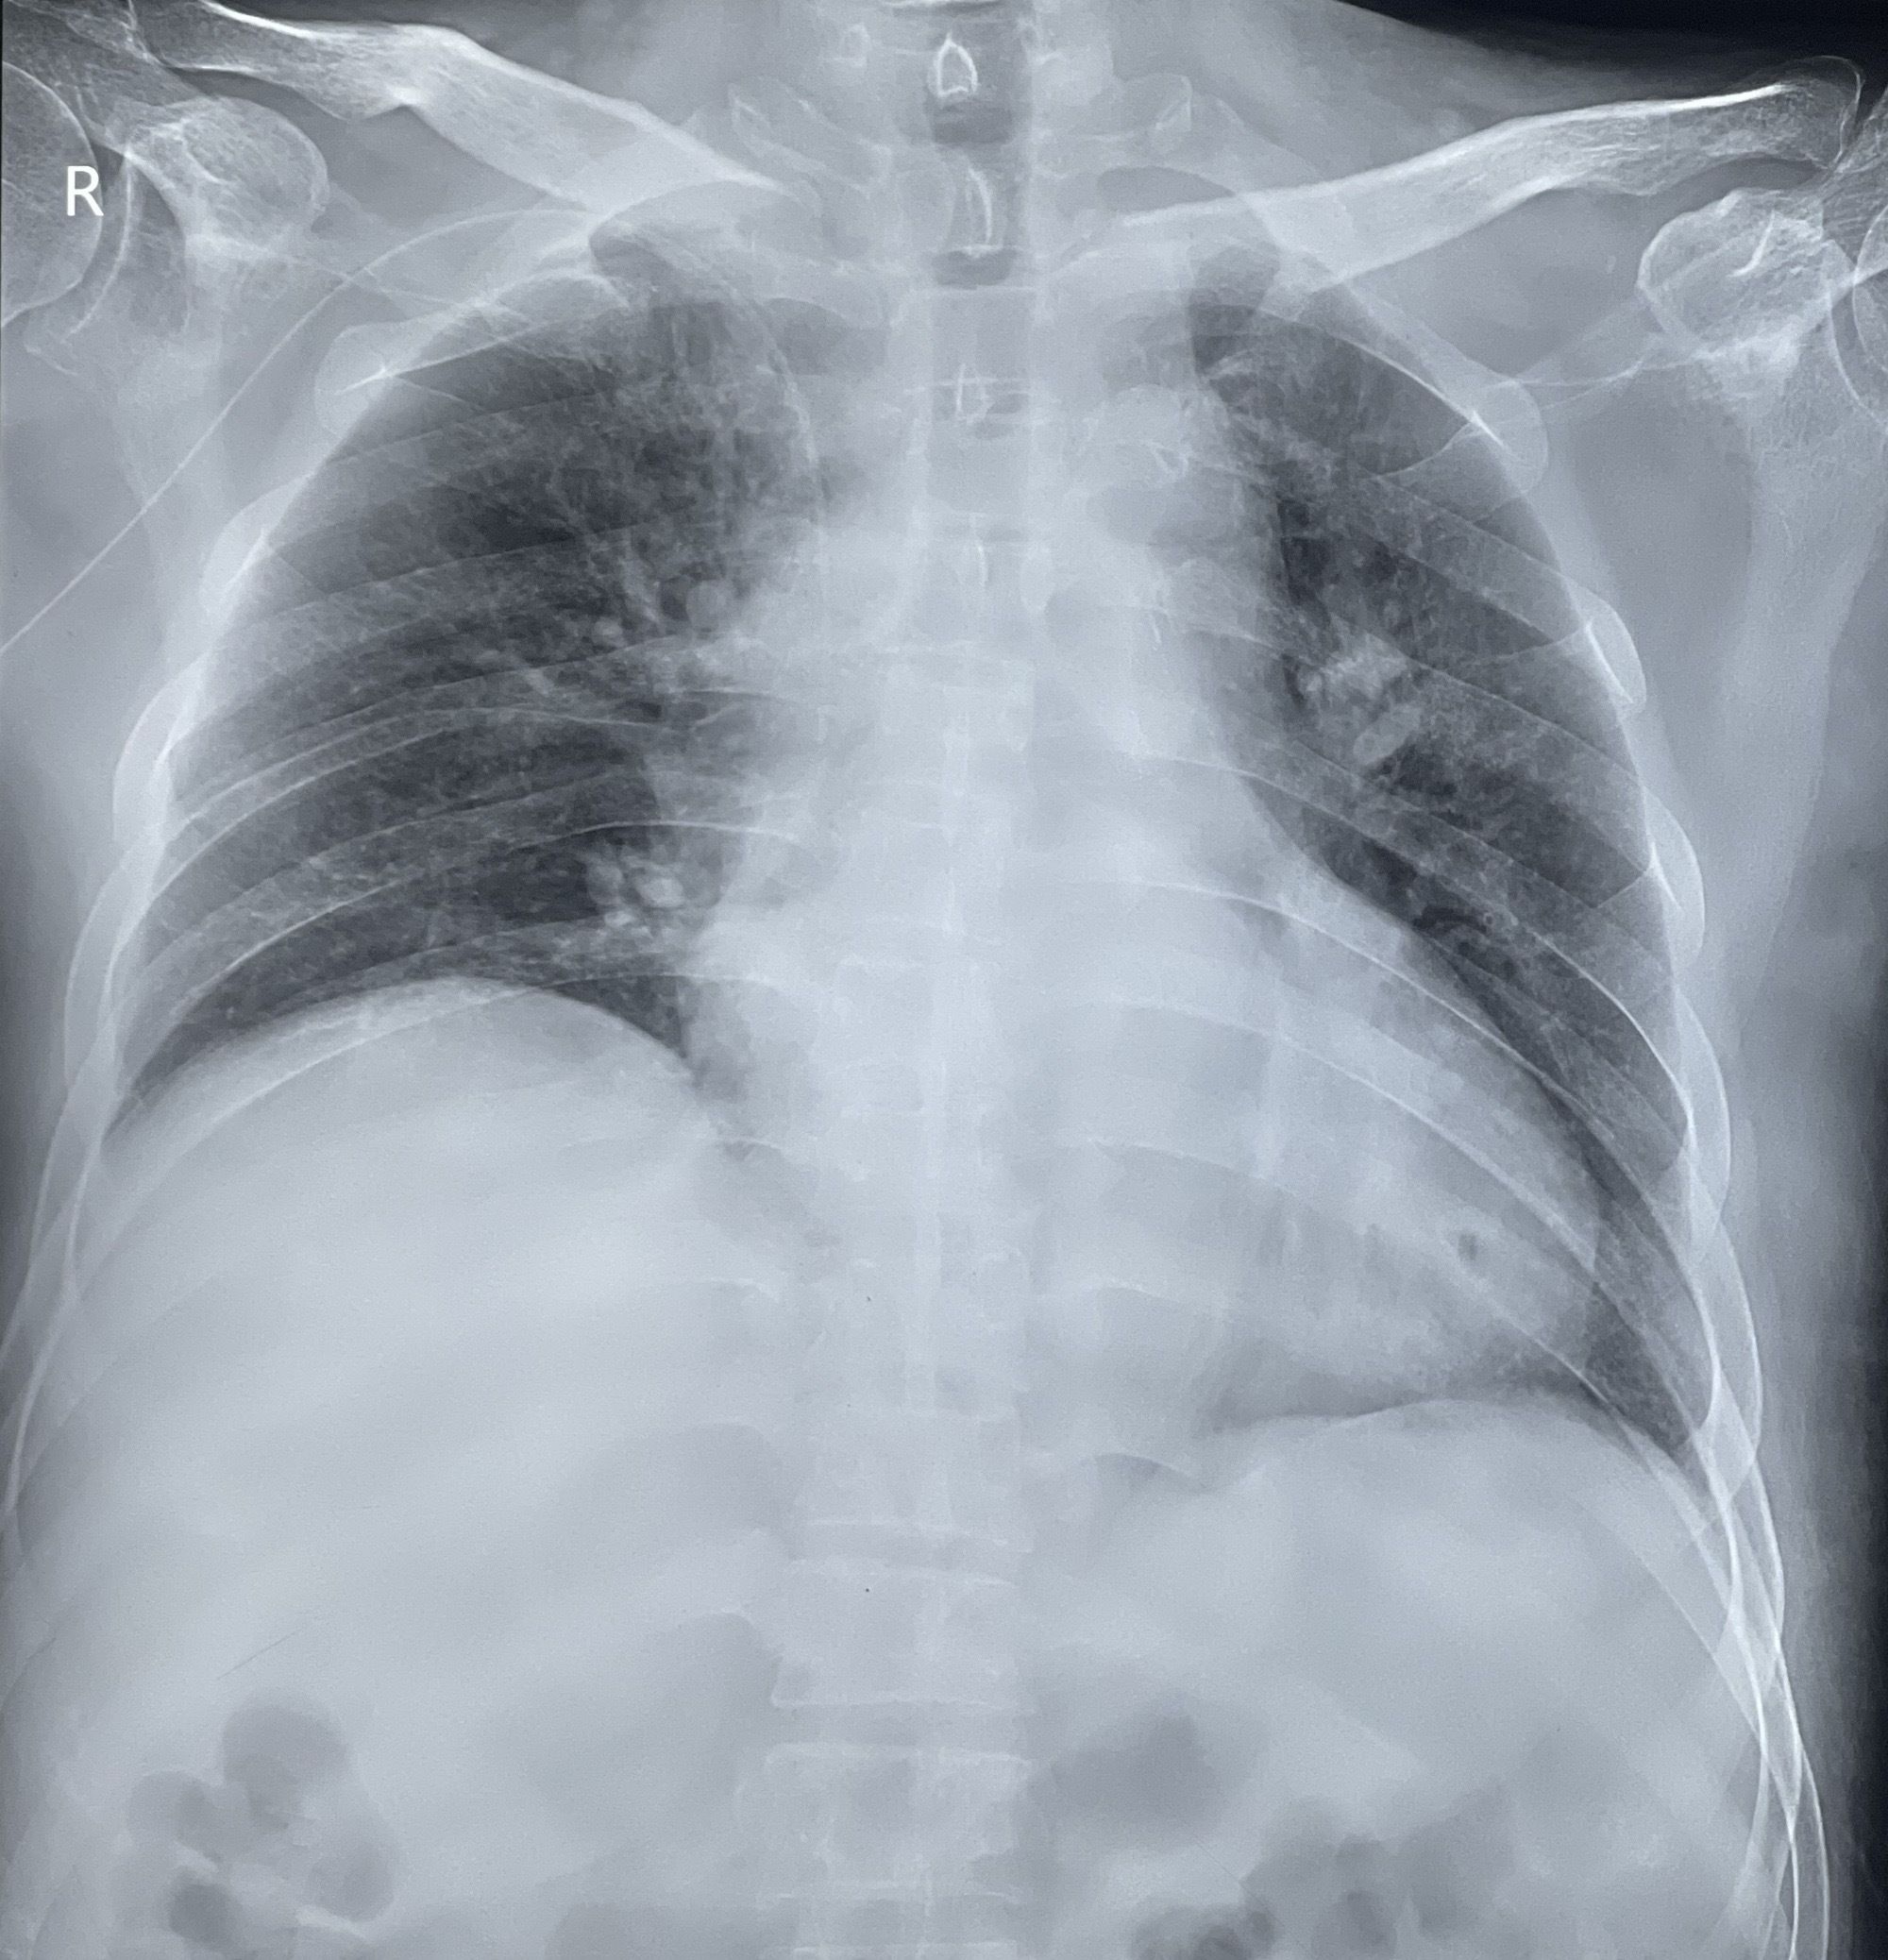

目前,X线胸片虽然是确定PICC导管尖端位置的金标准,但却是在置管后才能确认位置,无法实时定位导管尖端位置,一旦发生导管异位,不仅增加调整时感染的几率,还会延迟患者输液治疗的开始时间。

腔内心电定位技术是通过特制的心电导联线将PICC导管内导丝与心电监护仪连接,通过观察右心房P波特征性变化,可在置管过程中,第一时间实时识别导管尖端位置,减少了导管异位等并发症的发生,从而实现更精准、更快速的输液治疗,同时大大降低了反复穿刺给患者带来的痛苦和输液成本。